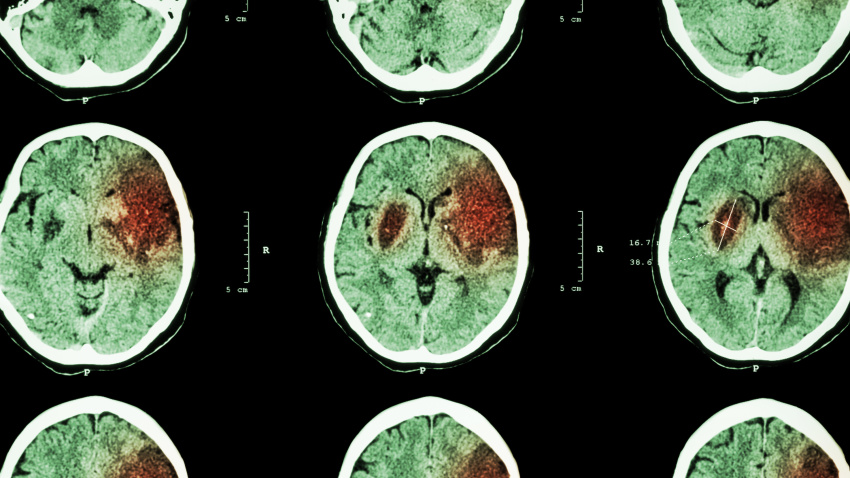

Imagen de recurso de un cerebro con daños por ictus

La investigación ha analizado datos de 6.258 participantes desde 1987. Durante el seguimiento, se identificaron 434 accidentes cerebrovasculares y 1.291 casos de fibrilación auricular. El análisis encontró que quienes usaban hilo dental tenían un 22% menos de probabilidad de ictus isquémico, un riesgo 44% menor de ictus cardioembólico (originado en el corazón) y un riesgo 12% menor de fibrilación auricular.

Un hallazgo relevante es que esta reducción del riesgo era independiente del cepillado regular y de las visitas al dentista, lo que sitúa al hilo dental como un factor clave en la prevención. El autor principal ha destacado que este hábito es "fácil de adoptar, asequible y accesible en todas partes", una ventaja para quienes consideran que el cuidado dental es "costoso".